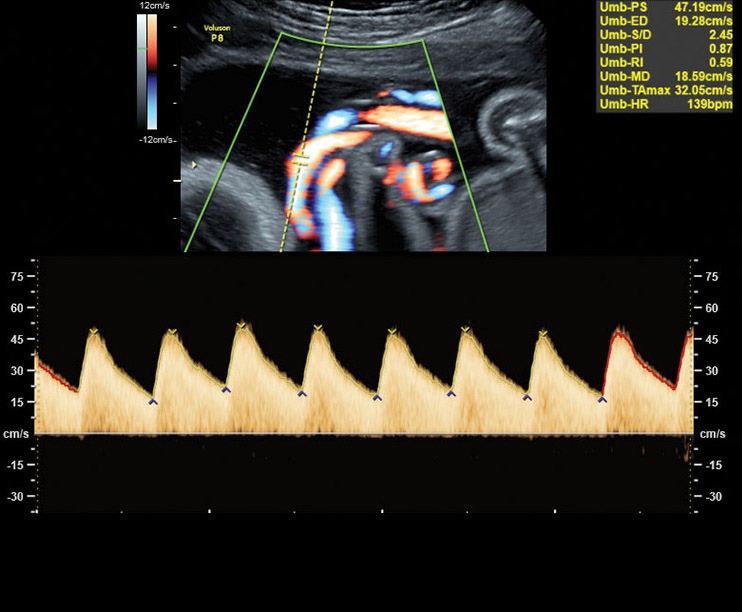

• Усовершенствованное цветовое доплеровское картирование: Эта функция позволяет получить более детальное изображение сердечно-сосудистой системы и ее функциональных систем. Она выводит обследование на новый уровень, обеспечивая более точную визуализацию и анализ данных.

Аппарат Voluson P8 сочетает простоту использования, высокую точность диагнозов и эффективность обследования в области акушерства и гинекологии. Он предоставляет медицинскому персоналу мощный инструмент для более точной диагностики и улучшения обслуживания пациентов.

• Акушерство и гинекология: Voluson P8 обеспечивает высокую точность диагностики беременности, оценку развития плода, обследование матки и яичников, а также другие акушерские и гинекологические исследования.

• Работа в В-, М-режимах, наличие импульсно-волнового, цветного допплеровского картирования, тканевого, энергетического и высокочувствительного направленного энергетического допплера (HD-Flow), тканевая гармоника

• Высокочувствительный допплер (HD-Flow), многолучевое сложносоставное сканирование (CRI), Speckle Reduction Imaging (SRI), SonoBiometry (автоматическое измерение BPD, AC, HC, HL, FL)